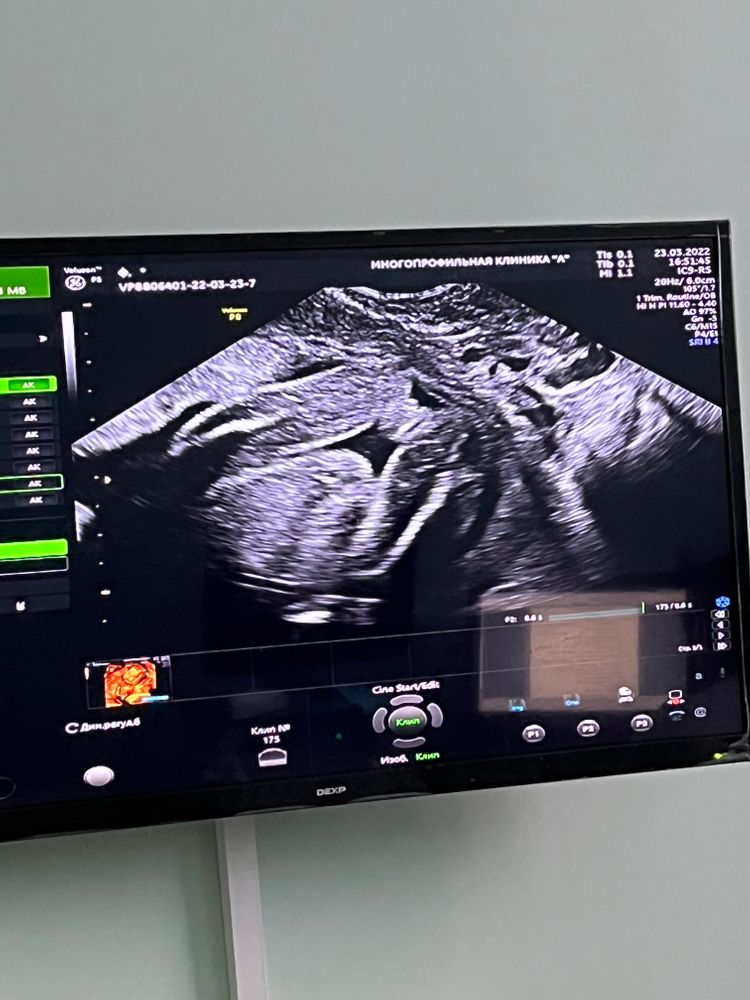

Марина, ох, значит и у меня девочка.... Столько переживаний было, скоро рожать, а я все сомневаюсь😄в Изображение 32 недели пошла точно чтоб узнать, а эта засранка ногу в колено согласно и пяткой закрыла промежность... Но потом немного отодвинул ногу. Сказали что похоже на девочку🤷‍♀️

16.07.2022